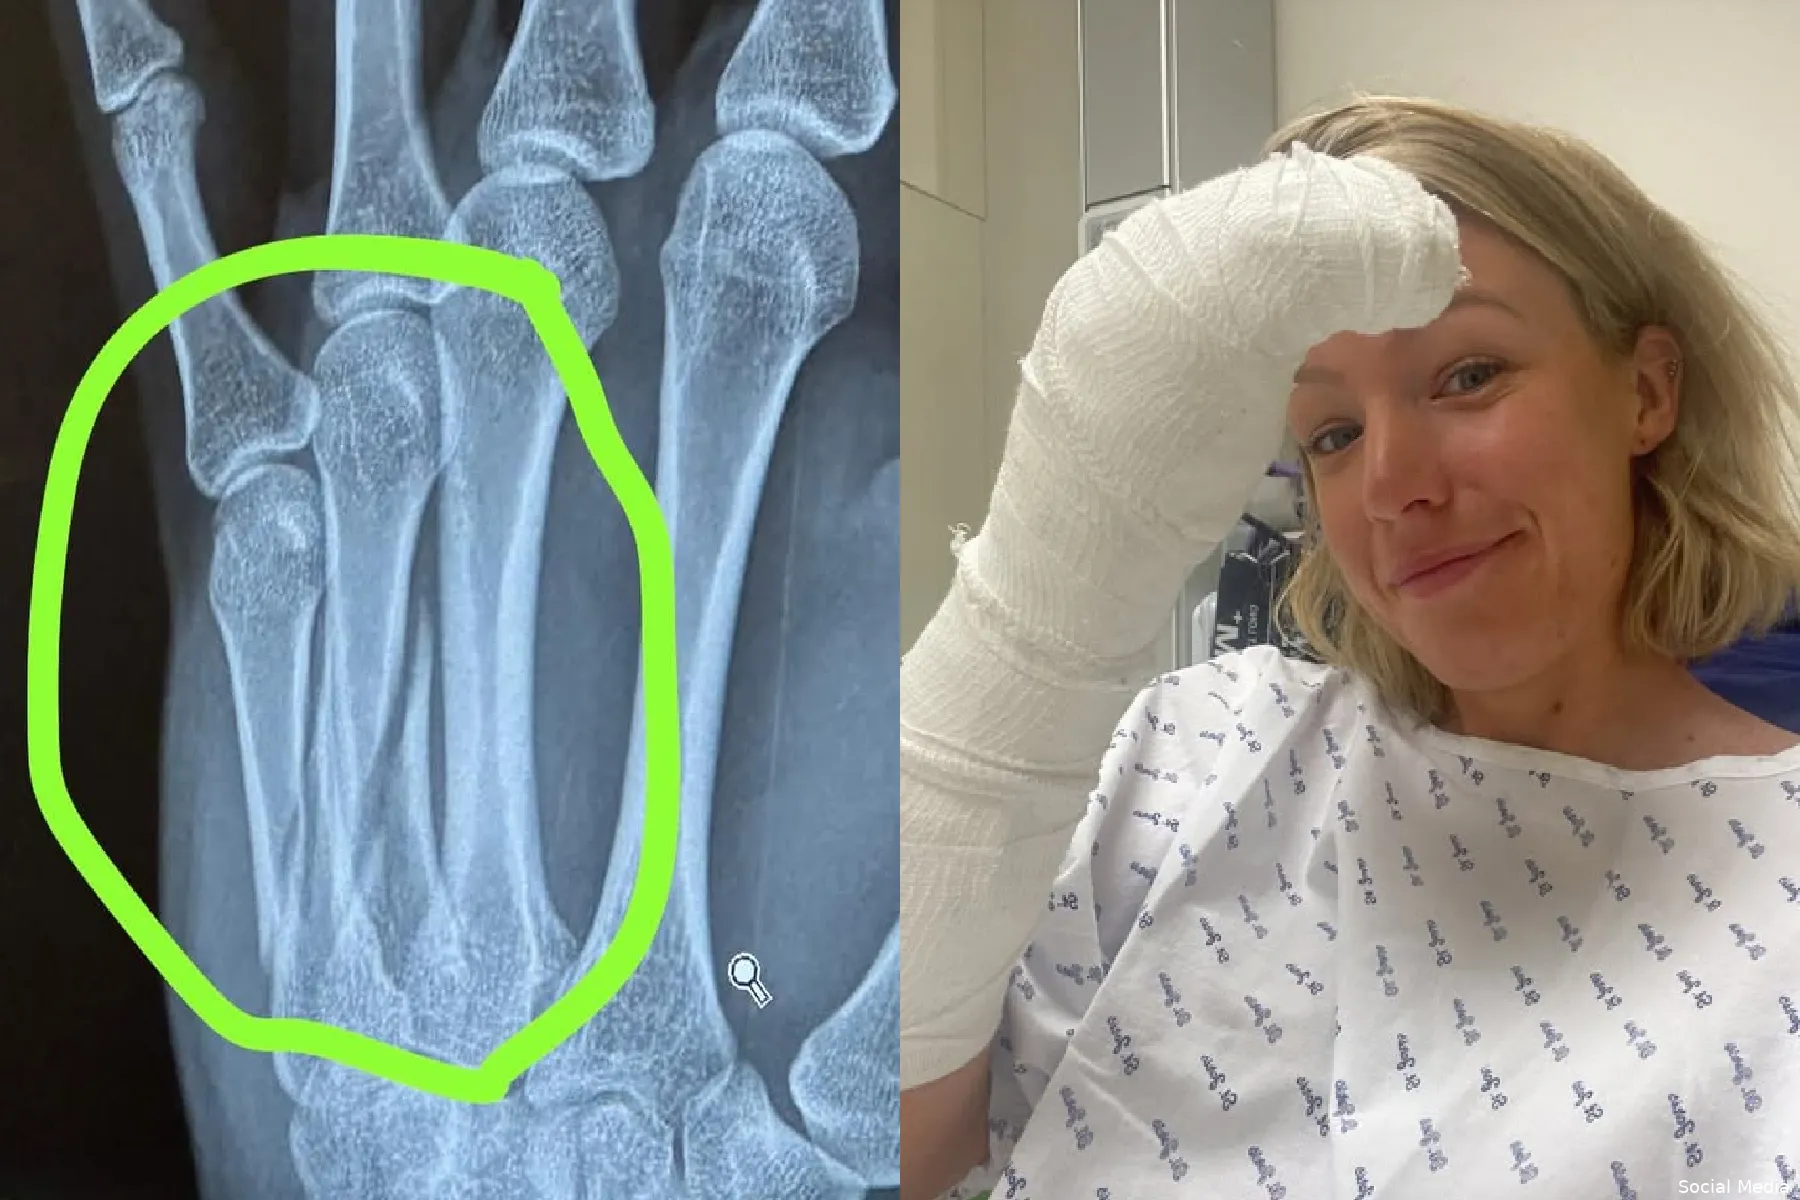

Worst liet op haar Instagram weten: 'Mijn dag startte heel goed, ik voelde me zoals in mijn laatste paar races', vertelt ze. 'Mijn conditie ging vooruit en iedere cross voelde ik me sterker. Maar het eindigde op een brute manier met een crash in de kuil van Zonhoven. Bij de val brak ik twee botten in mijn hand, dus nu is het tijd voor een operatie op dinsdag.'

Een flinke tegenvaller dus voor Worst, die eventjes uit zal liggen. Hoe lang ze precies niet kan koersen liet ze achterwege. Ze deed met de besten mee op zaterdag, maar buiten beeld knalde ze hard op de grond. In een kort statement van haar ploeg werd gesteld: 'Onderzoeken in het AZ in Herentals hebben twee gebroken middenhandsbeentjes in de linkerhand aangetoond. De botten zullen operatief worden gerepareerd.'

'Het is de vroeg om te zeggen hoe lang ze eruit ligt', zo valt er verder te lezen. 'Maar dit is een grote tegenslag voor Annemarie, die in excellente vorm was in deze cruciale fase van het cross-seizoen.' na de operatie op dinsdag volgde een kleine glimlach van Worst op Instagram: 'Vanaf nu is de enige weg omhoog, tijd om terug te k